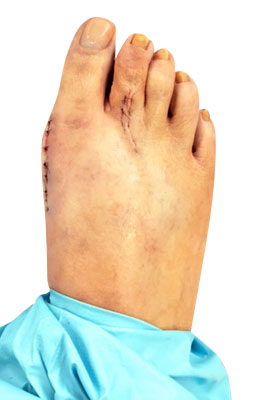

Before

Lapidus Forever Bunionectomy™ and Hammertoe Correction before

After

Lapidus Forever Bunionectomy™ and Hammertoe Correction after

Lapidus Forever Bunionectomy™ and Hammertoe Correction

George is a 62-year-old businessman who presented with a sore on his second toe from rubbing on his shoes. We decided to correct his foot as a whole and performed several orthopedic surgical procedures as she had both types of bunions. He chose our Lapidus Forever Bunionectomy™, a hammertoe correction and an osteotomy for his Tailor’s Bunion (bunionette). George was weight bearing on his foot at two weeks and back in regular shoes at 8 weeks with no pain and full function.